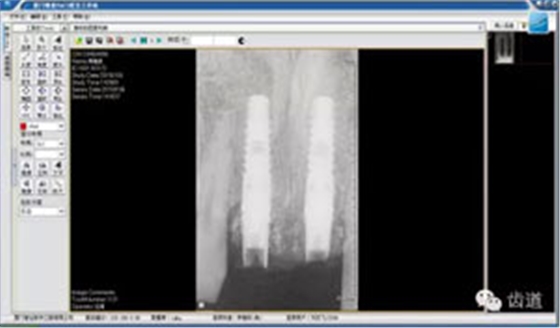

放射檢查:11,21根中三分之一至根尖三分之一處折斷。

術(shù)前放射片